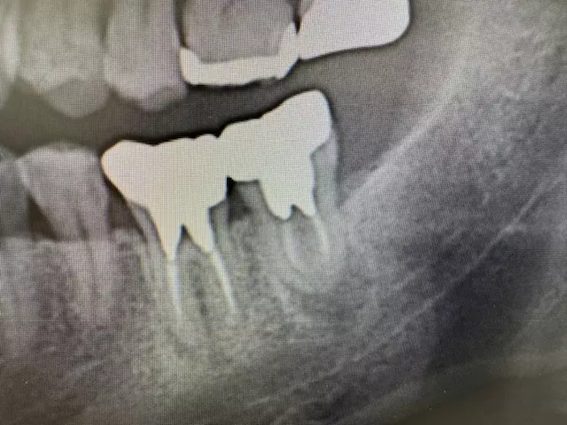

| 主訴 | 左上6番部 抜歯即時インプラント埋入。 |

| 治療内容 | 左上6番部インプラント埋入。 歯根破折により要抜歯。 抜歯即時埋入。 上顎洞まで1.5㎜。 |